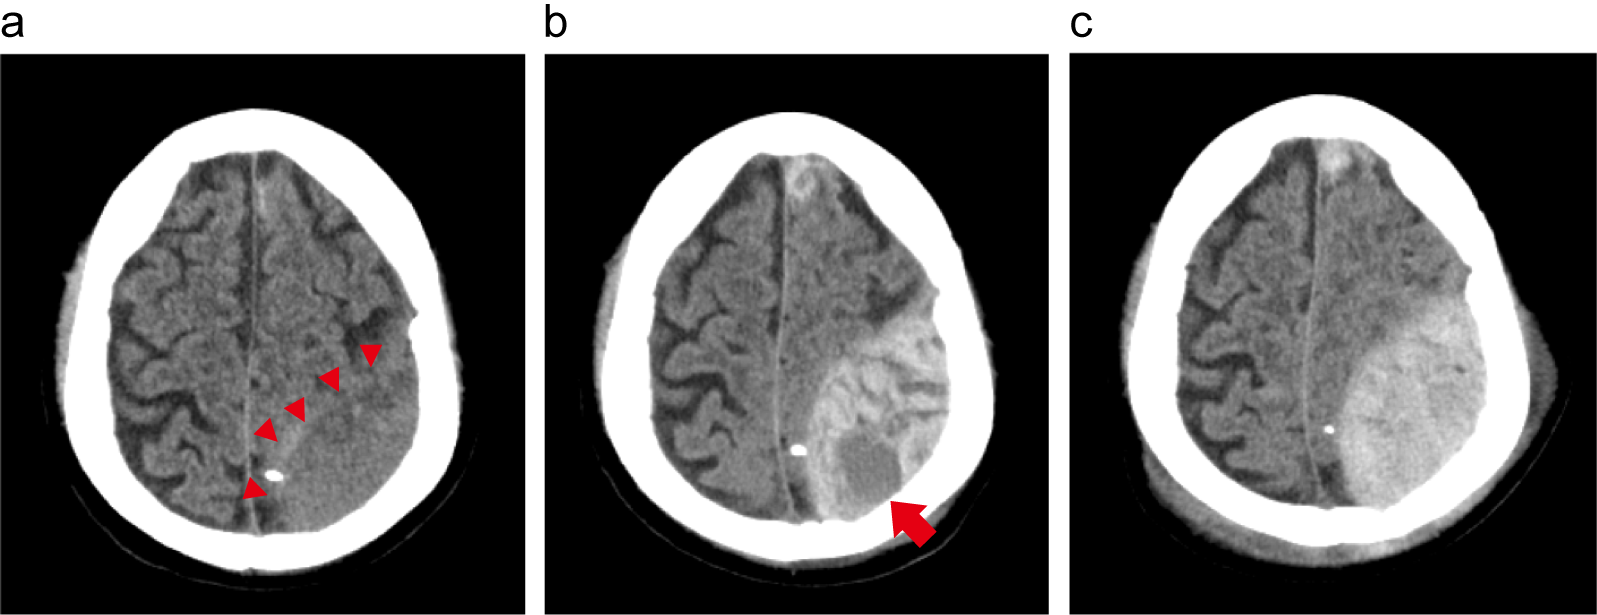

急性硬膜外血腫の症例

70歳代、男性。アルコール性肝硬変終末期で通院中に転倒し搬送された。

a. 受傷直後の頭部CT。ひだり頭頂部に低吸収値の急性硬膜外血腫(矢頭)を認めた。明らかな局所症状はなく、保存的加療目的に入院した。

b. 入院2時間後、みぎ片麻痺の進行があり再検した頭部CT。血腫の増大を認め、高吸収値となった血腫内部の一部に低吸収値を伴っていた(矢印、swirl sign)。ひだり前頭葉には小さな脳挫傷性血腫も認めた。手術も検討されたが、血小板低値、凝固能異常や低アルブミン血症などで全身状態が不良であり、家族の積極介入希望もなかったため、保存的加療継続の方針となった。

c. 受傷翌日の頭部CT。血腫の増加がみられたが、神経症状の悪化はなく、保存的加療を継続した。